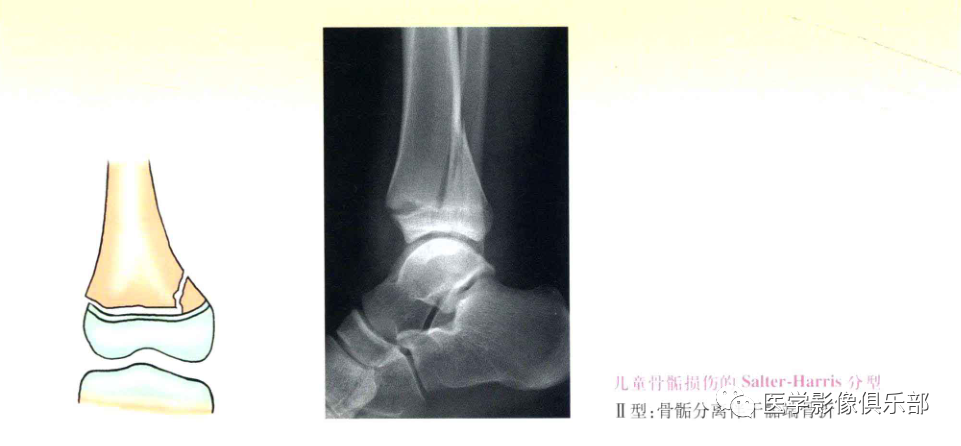

Ⅱ型:骨骺分离伴干骺端骨折;